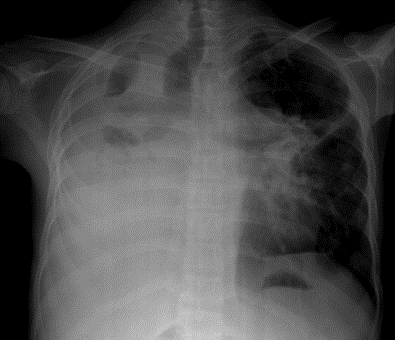

Case 2 (Right ventricular endomyocardial fibrosis in Tuberculosis) A 23-year old male was admitted with sudden onset of ascites for one-month duration. He was treated for pulmonary tuberculosis 3 years back with a positive sputum AFB (acid fast bacilli). Blood chemistry revealed as ( Total count-7400 cells/cu.mm of blood ( normal-4000 to 11000 cells/cu.mm of blood), polymorphs -70% (normal- 40 to 75 %), lymphocytes-22%(normal-20 to 40%), eosinophils-8% (normal- 1 to 4%), ESR (erythrocyte sedimentation rate)-10 to 22 mm/hour ( normal- 0 to 15mm/hour), platelets-2.5 lakhs/cu.mm of blood and a mild elevation of serum bilirubin-total-2mg/dl(normal---up to 1.2 mg/dl) direct-1.2mg%(normal—upto—0.3 mg/dl), indirect-0.8mg%(normal – upto 0.9 mg/dl). Total serum proteins 5.2gm% (normal -6.6 to 8.3 gm/dl), albumin-3.2gm% (normal- 3.5 to 5.0 gm/dl), globulin -2.0gm%(normal 2.5 to 3.5 gm/dl ), urea-39 mg%(normal 15-50 mg/dl), creatinine-0.1mg%(normal- 0.7 to 1.4mg/dl), sugar-112 mg/dl random (normal – 80 to120 mg/dl- random sample). Ascites fluid tapping revealed an exudate (protein-3 gm%) and cytology revealed no malignant cells. Ascites fluid adenosine deaminase (ADA)activity revealed 10.4 U/L (normal < 40>Figure 8. His pulse rate was 108 bpm and blood pressure 100/70 mmHg. Auscultation revealed clear lung fields and no cardiac abnormalities. ECG revealed no arrhythmias and X-ray chest showed right- sided pleural effusion and extensive calcification over the cardiac shadow as shown in Figure 9. Transthoracic echocardiography revealed apical fibrosis of right ventricle, moderate pericardial effusion, right atrial dilatation as shown in Figures 10 and 11, suggesting right ventricular endomyocardial fibrosis and severe tricuspid regurgitation as in Figure 12 indicates coexisting pulmonary hypertension due to pulmonary damage caused by tuberculosis as shown in Figure 13 and free RV outflow tract as in Figure 15. Patient was treated with antituberculous drugs, antifailure measures such as digoxin and diuretics, ascites fluid tapping and antibiotics. He showed mild improvement in his symptoms.

Figure 9: X-ray chest PA (postero-anterior) view showing right-sided pleural effusion and endocardial calcification over the left ventricle in burn- out stage of EMF (endomyocardial fibrosis).

Endocardial calcific deposits can be present involving diffuse areas of the ventricles and Cockshott et al described this feature in 1967. Calcification, an impressive finding on imaging denotes a burnt-out phase of endomyocardial fibrosis (EMF) and confirming the malignant nature of the disease. Chest X-rays show varying degrees of cardiomegaly and at times typical endocardial calcifications in the left and right ventricles as shown in Figure 9 (left ventricular endocardialcalcification) [24- Figure 2(a)] and in Figure 16 (right ventricular endocardial calcification)[25- Figure 2 (c)- shows calcification in both ventricles], [26].

A large pericardial effusion is often present and noted as another peculiar feature of this disease [27]. Pericardial effusion and ascites dominate the clinical picture of right ventricular EMF [28], [29], [30]. Etiology of pericardial effusion is possibly inflammatory and EMF is to be considered as ‘pancarditis’ since all the layers are involved. Adhesions between the parietal and visceral layers of the pericardial sac may develop and visible as strong fibrotic strands as shown in Figures 29. A right ventricular EMF presented with massive pericardial effusion was detected in a 85 –year old female as shown in Figure 16, 17 and 29[31]. Cardiomegaly can be exaggerated by pericardial effusion, and pleural effusion is also a common finding as shown in Figure 9 [16-Figure 2]. Giant ascites in EMF is not fully explained by congestion alone and it is due to peritoneal inflammation and reduced reabsorption of peritoneal fluid, caused by fibrosis since the fluid is an exudate with predominant lymphocytes. The triad of elevated JVP (Jugular venous pressure), ascites and hepatomegaly formed the hallmark of right ventricular EMF.